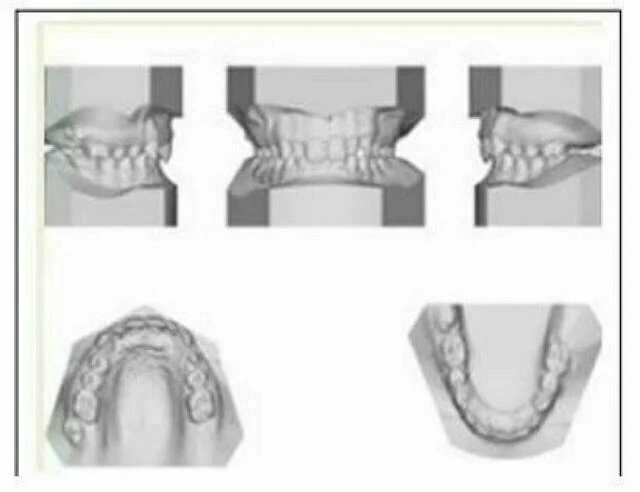

9. Mẫu hàm nghiên cứu

Trong chỉnh nha, chất lượng mẫu hàm sẽ ảnh hưởng đến những gì người khác đánh giá công việc của bạn. Vì lý do này, để tạo danh tiếng về sự chuyên nghiệp của bạn, hãy CHỈ làm mẫu hàm nghiên cứu của bạn ở tại labo chỉnh nha. Quy trình này sẽ chuẩn hóa chất lượng mẫu nghiên cứu (đây gọi là chuẩn hóa chuyên môn), đòi hỏi thời gian và khá nhiều kỹ thuật. Mẫu nghiên cứu kiểu này cần có thạch cao chỉnh nha chuyên dụng, máy mài mẫu với bàn đế được tạo góc theo tiêu chuẩn.

9.1. Cách làm:

1. Lấy dấu bằng alginate trong khay lấy dấu chỉnh nha. Khay dùng lấy dấu cầu và chụp không mở rộng đủ để lấy đủ các chi tiết dùng cho chỉnh nha.

2. Bọc dấu vào khăn giấy ướt và đặt bông cuộn ướt vào trong dấu.

3. Đặt dấu và sáp cắn (lấy dấu cắn trung tâm trên miệng ngay tại ghế răng) trong túi có khóa kéo để duy trì độ ẩm. Liên lạc với labo.

4. Mẫu hàm nghiên cứu từ labo gửi lại sẽ có chất lượng tuyệt vời. Lấy tiền của bệnh nhân cao hơn so với phí labo bình thường.

9.2. Quản lý mẫu:

Bảo quản mẫu hàm trong hộp và xếp ngăn nắp tại phòng mạch. Cần đánh mã số cho mỗi bệnh nhân và bảo quản mẫu theo mã số này. Ví dụ số của hệ thống là 04002. Đây là dấu nghiên cứu lấy lần thứ hai vào năm 2004. Ghi mã số vào form trong bệnh án ghi tay ở góc trên bên phải (mã số #). Khi sử dụng phần mềm quản lý bệnh nhân thì bệnh nhân sẽ tự động có mã riêng khi nhập file lần đầu tiên.

Cần chú ý rằng hiện giờ dịch vụ mẫu nghiên cứu điện tử đã có ở một số labo đặc biệt, dấu được gửi đến labo, từ đó có mẫu nghiên cứu bình thường, sau đó xưởng quét 3D mẫu này. Bạn có thể download file mẫu nghiên cứu này vào phần mềm để làm việc. Đây là do bạn chọn xem bạn có muốn nhận mẫu nghiên cứu bằng thạch cao hay không. Một vài bác sĩ không muốn có rắc rối khi phải lưu mẫu.